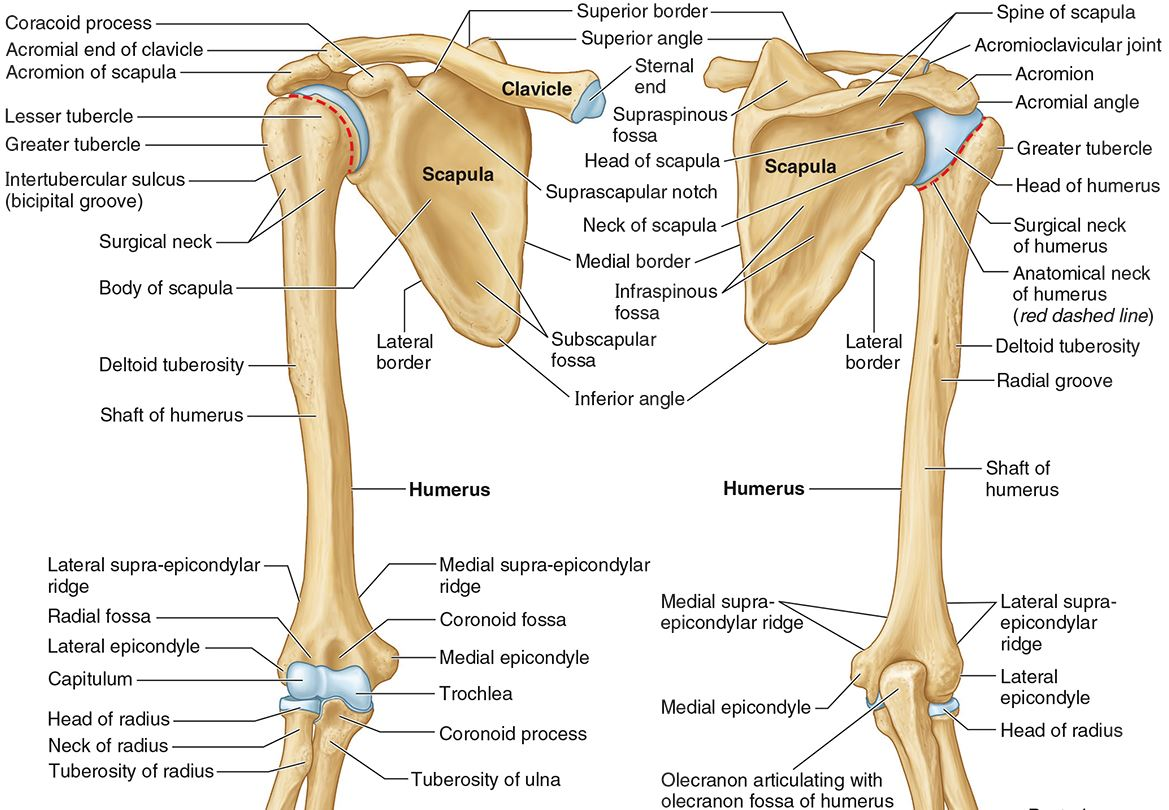

What part of the humerus is this?

The head of the humerus articulates with the scapula at the glenohumeral joint.

What part of the humerus is this?

The anatomic neck is an indentation distal to the head and provides an attachment for the fibrous joint capsule of the glenohumeral joint.

What part of the humerus is this?

The greater tubercle lies lateral and distal to the anatomic neck.

What part of the humerus is this?

The lesser tubercle lies on the anterior/medial side of the humerus, just distal the anatomic neck.

What part of the humerus is this?

The intertubercular (bicipital) groove lies between the greater and lesser tubercles.

What part of the humerus is this?

The surgical neck is a narrow area distal to the tubercles. It is a common site for proximal humerus fractures.

What part of the humerus is this?

The humeral shaft features the deltoid tuberosity laterally for the distal insertion of the deltoid muscle.

What part of the humerus is this?

The radial groove is an oblique depression that contains the radial nerve and deep brachial artery.

Which parts of the humerus is this?

The medial and lateral epicondyles are distal prominences to which many forearm tendons attach, near the elbow joint.

Which parts of the humerus is this?

The medial and lateral supracondylar ridges extend superiorly from the medial and lateral epicondyles.

Which parts of the humerus is this?

The trochlea and the capitulum (the condyles) are the most distal surfaces of the humerus, where it articulates with the forearm bones at the elbow joint

What part of the humerus is this?

The olecranon fossa is a posterior depression above the trochlea that receives that olecranon process of the ulna

What part of the humerus is this?

The coronoid fossa is an anterior depression above the trochlea that receives that coronoid process of the ulna.